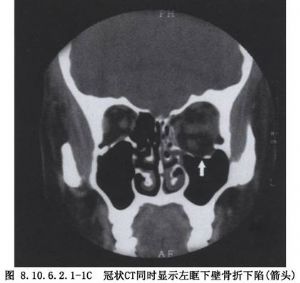

2.X线及CT检查可以证实眶底骨折的部位、形态、范围、有无眶内容脱出及是否合并有眶内、外、上壁骨折者。